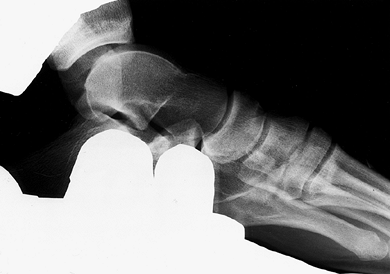

radiographs (Fig. 95.1 and Fig. 95.2).

If desired, 15 ml of 1% lidocaine can be injected into the ankle for

pain relief. The amount of anterior talar translation is measured as

the distance from a constant point on the posterior aspect of the talus

to the posterior lip of the tibia. Talar tilt is measured as the degree

of angulation of the superior aspect of the talus as referenced against

the neutral position of tibial plafond.

| Figure 95.1. Stress radiograph of a positive anterior drawer test (ADT). |